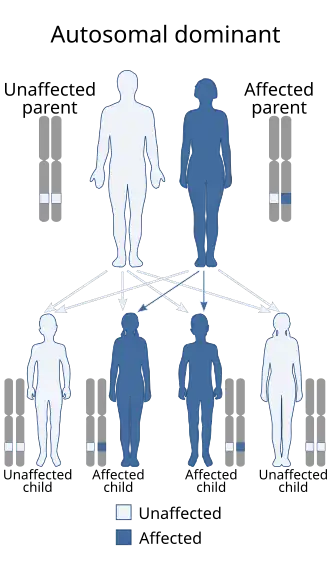

Sprengel's deformity (also known as high scapula, scapular hypoplasia, or congenital high scapula) is a rare congenital skeletal abnormality where a person has one shoulder blade that sits higher on the back than the other. The deformity is due to a failure in early fetal development where the shoulder fails to descend properly from the neck to its final position. Majority of the cases are sporadic with very few having autosomal dominant inheritance.[1]